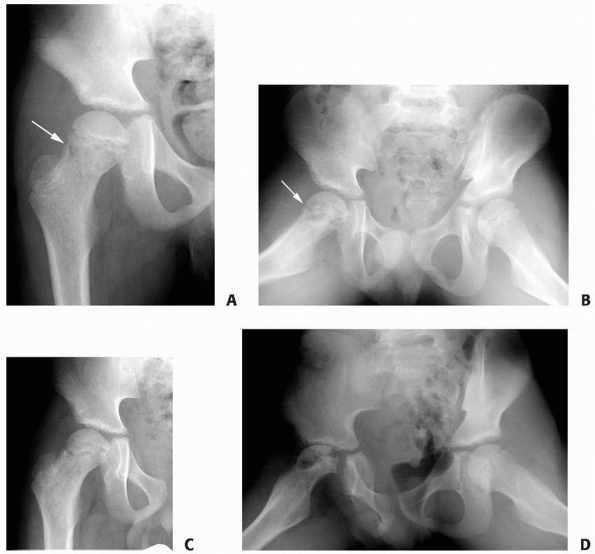

FIGURE 6-8 A 9-year-old boy presented with low back pain and abdominal discomfort. On plain radiographs of the abdomen (A), an expansile lesion involving the left posterior elements of L1 was visualized. Axial T2-weighted MRI (B) and an axial CT scan image (C) show the microfractures at the pedicle and lamina level (arrow)

and the fluid-fluid levels. The patient underwent open biopsy that confirmed the diagnosis of aneurysmal bone cyst, followed by a 4-step approach excision and bone grafting. Limited instrumentation of the spine was performed due to stability compromise (D). (Permission) |